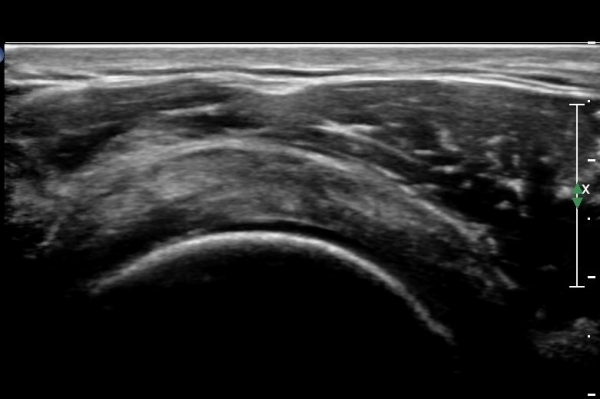

±Ø»ó°Ç Á¾´Ü¸é°Ë»ç¿¡¼­ ±Ø»ó°Ç ½ÉÃþÀÇ °Ç¿° ¼Ò°ß°ú Á¡¾×³¶³» ¼ö¾×Àú·ù°¡ °üÂûµÊ(»çÁø 7, 9).

ÀÌµÎ¹Ú±Ù°Ç Á¾´Ü¸é°Ë»ç¿¡¼­ Á¡¾×³¶³» ¼ö¾×Àú·ù´Â ´õ¿í ¶Ñ·ÈÇÔ(»çÁø 10).